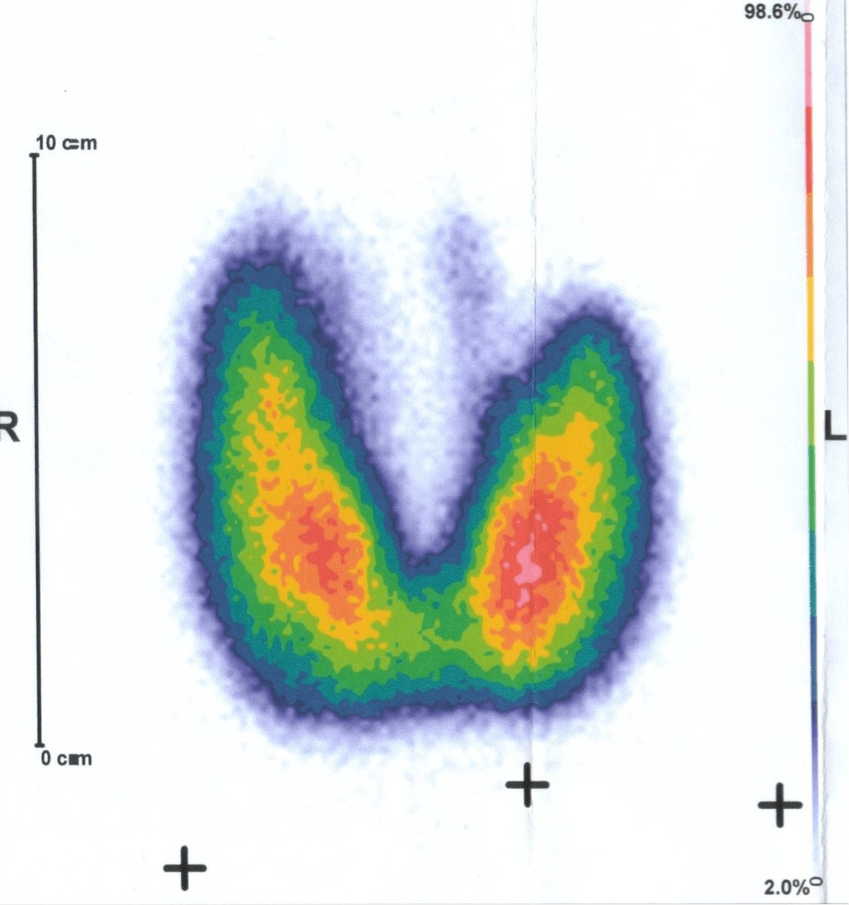

- Traitement par iode radioactif : il consiste à détruire une partie hyperactive de la thyroïde par irradiation interne.

- Dans un deuxième temps un traitement par iode 131 en comprimé appelé IRAthérapie peut compéter le traitement des cancers papillaires et folliculaires.

- Le goitre toxique multi-nodulaire : présence d’un goitre thyroïdien avec plusieurs nodules sécrétant des hormones thyroïdiennes.

- Adénome toxique : présence d’un seul nodule thyroïdien qui sécrète des hormones thyroïdiennes.